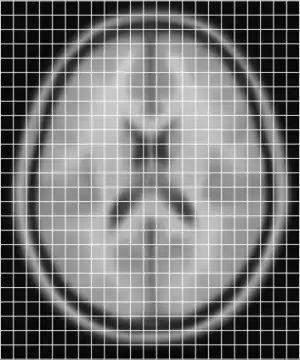

In order to get a better understanding of how mni_autoreg or indeed linear registration works, here is a simple example. Suppose we have an image of an individual and wish to align this with a model. These two images are shown below, the individuals image on the left (indiv.mnc) and model (model.mnc) on the right. Note that both of these files have different sampling and voxel sizes as illustrated by the white lines